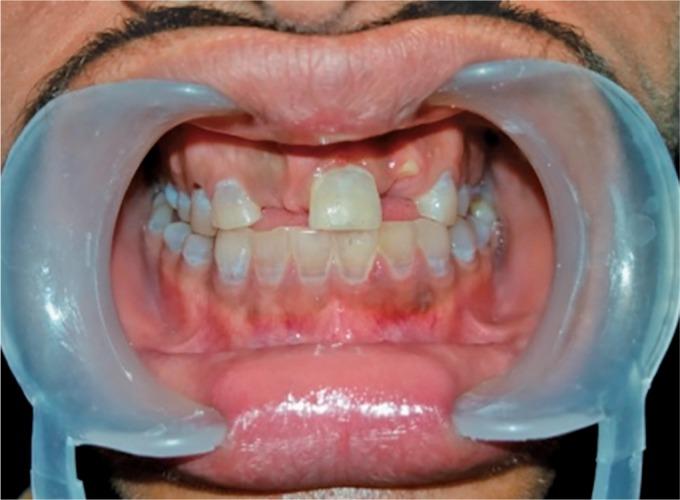

Dentinogenesis imperfect is a hereditary dentin defect leading to discoloration as well as early tooth wear. Timely diagnosis and treatment are required to prevent further tooth loss. Two patients reported to the department of pediatrics dentistry with dentinogenesis imperfecta (DI). In the first case, patient complained of discoloration of both primary and permanent teeth and delayed eruption of permanent teeth. In the second case report, patient reported with mobile anterior tooth and missing teeth due to extraction of mobile teeth. Extraction was followed by space maintainers in the first case, and extraction was followed by partial denture in the second case. Both the patients and their parents were happy with the treatment provided.

牙本质发育不全是一种遗传性牙本质缺陷,可导致牙齿变色以及早期磨损。需要及时诊断和治疗以防止进一步的牙齿脱落。两名患有牙本质发育不全(DI)的患者到儿童牙科就诊。在第一个病例中,患者主诉乳牙和恒牙均变色,恒牙萌出延迟。在第二个病例报告中,患者报告前牙松动且因拔除松动牙导致牙齿缺失。第一个病例在拔牙后使用了间隙保持器,第二个病例在拔牙后使用了局部义齿。患者及其父母对所提供的治疗均感到满意。